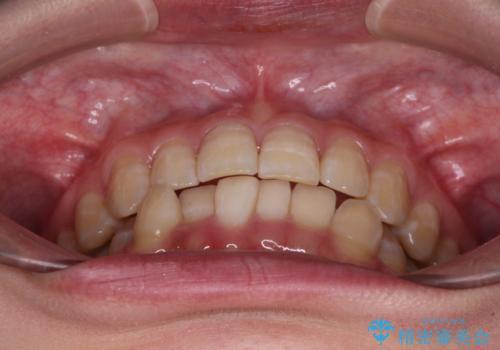

下顎前歯のデコボコが集中しており、奥歯の咬み合わせは、上顎に対して下顎が前方位にある状態でした。下顎の歯列を後方へ移動させる治療はインビザラインの得意とするところですので、1年程度で無事に治療を終えることができました。

【モニター】下顎前歯のデコボコをインビザラインできれいに